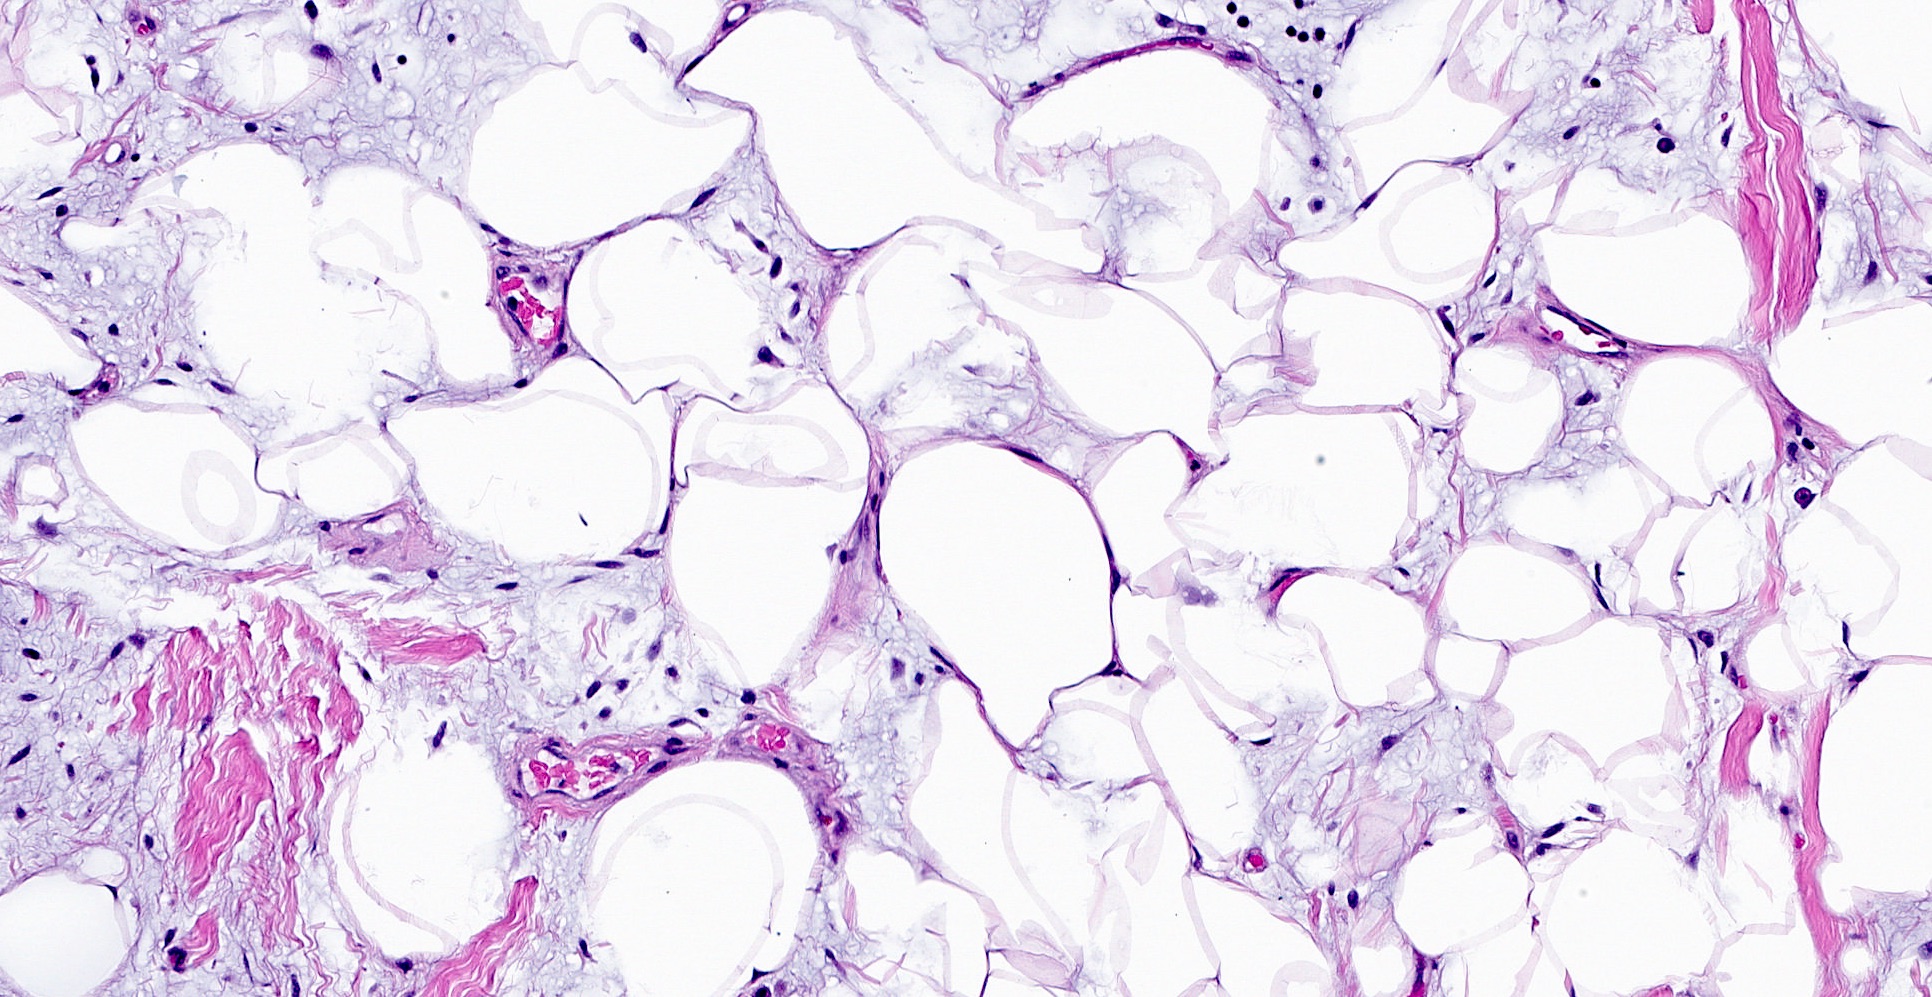

Microscopic (histologic) images

- Lipomatous: abundant adipocytic component